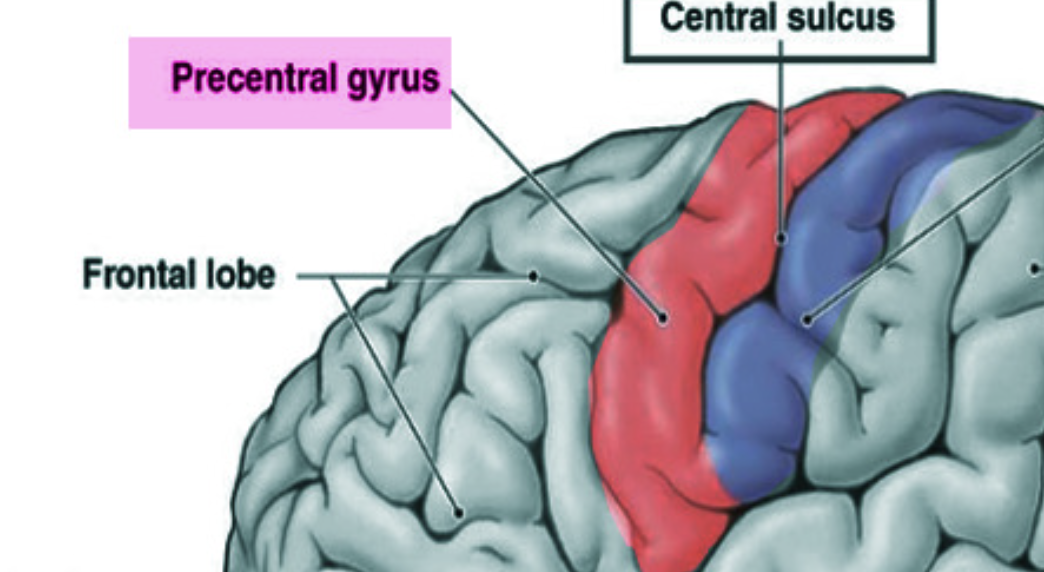

Which gyrus contain the primary motor cortex (where stimulation causes movement)

Precentral gyrus (primary motor cortex)

What are the ridges (folds) on the cerebrum called?

Gyrus/Gyri (Peak of the sunchip)

What are the grooves(valley) on the cerebrum called?

Sulcus/Sulci valley between the peak